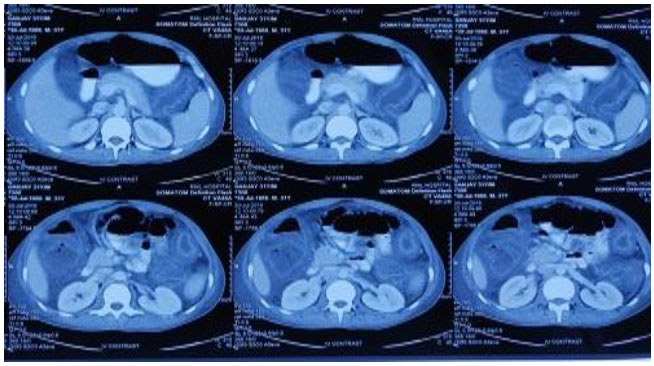

Two days later, he developed abdominal distension and on examination had guarding. Bowel sounds were sluggish. Repeat hemogram showed total leucocyte count of 30,000/mm3 with 88% polymorphonuclear cells. X-ray abdomen had no multiple air fluid levels (Figure 1 and Figure 2). Ultrasonography (USG) abdomen showed ascites and dilated bowel loops with loss of gut signature. Ascitic fluid showed more than 1000 cells/mm3 with 95% polymorphonuclear cells, sugar 119 mg, protein 2.81 g/dL, lactate dehydrogenase (LDH) 633 mg/dL, and serum ascites albumin gradient (SAAG) 0.46 suggestive of secondary bacterial peritonitis. Ascitic fluid culture was sent. Contrast-enhanced computed tomography (CECT) abdomen showed large bowel edema with small bowel dilatation suggestive of diffuse ischemic colitis (Figure 3).

Figure 3: CECT abdomen: large bowel edema and small bowel dilatation suggestive of diffuse Ischemic colitis.